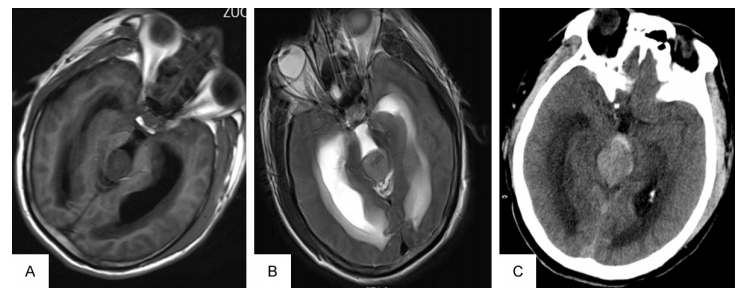

一名23岁男性,既往健康,有进行性头痛、呕吐和视力模糊病史。他在医院就诊前一天头痛加剧。神经学检查除了视力下降和双侧乳头水肿外,未见其他异常。CT显示松果体区等致密病变伴阻塞性脑积水(图1A)。MRI显示松果体区域肿瘤直径2.6 cm*3.1 cm*2.9 cm, t1加权图像低信号,t2加权图像轻度高信号(图1B)。采用德尔塔分流试剂盒进行脑室-腹腔分流手术以减轻患者的脑积水。分流术5小时后,病人恶化为深度昏迷状态,并无脑干反射。立即CT显示三脑室大量瘤内出血,该脑室破裂进入侧脑室(图1C)。由于他的神经系统状况不佳,没有进行减压手术,他后来去世了。

图1。CT及横t2加权MRI显示松果体区肿瘤合并梗阻性脑积水(a及B)。CT显示三脑室大量瘤内出血并破裂进入侧脑室(C)。